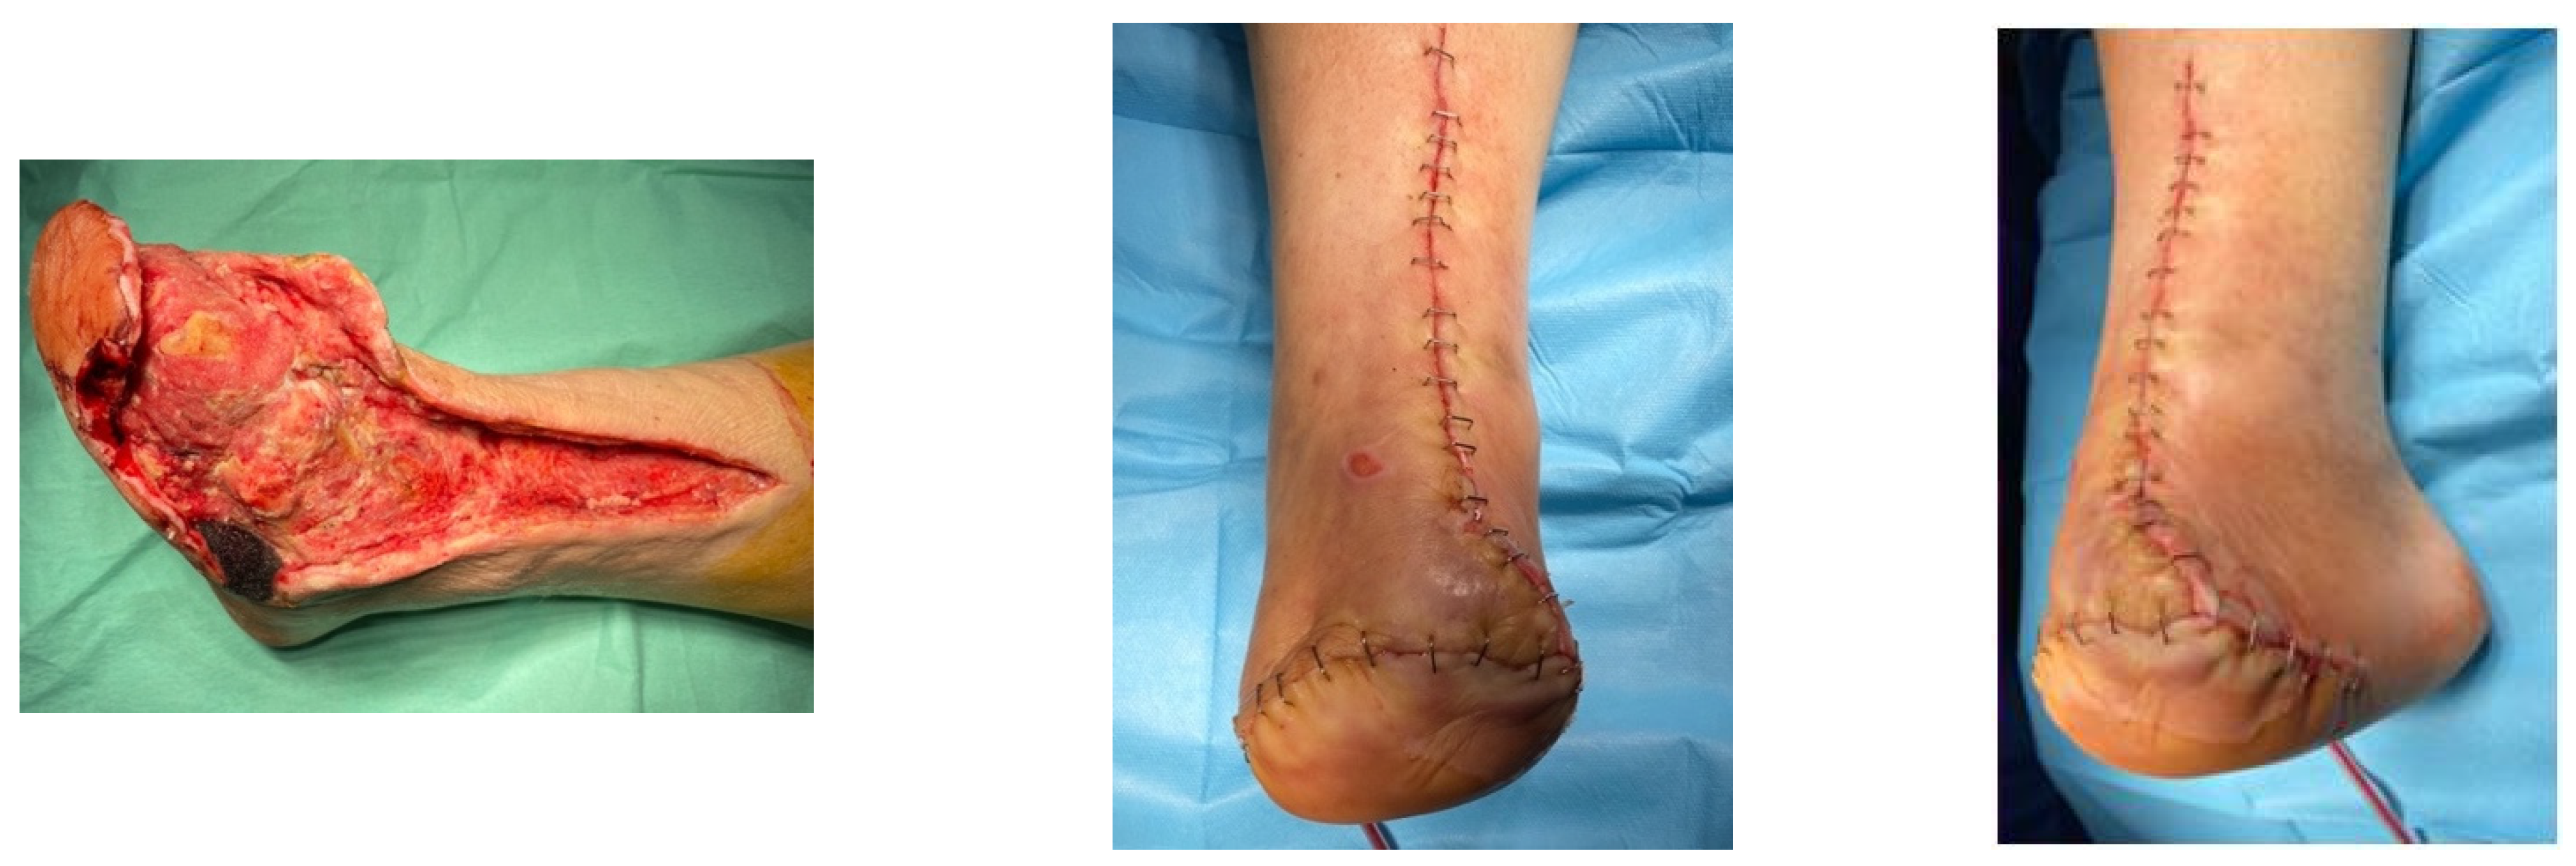

4.1. Case 1—Direct Revascularization-Minor Amputation